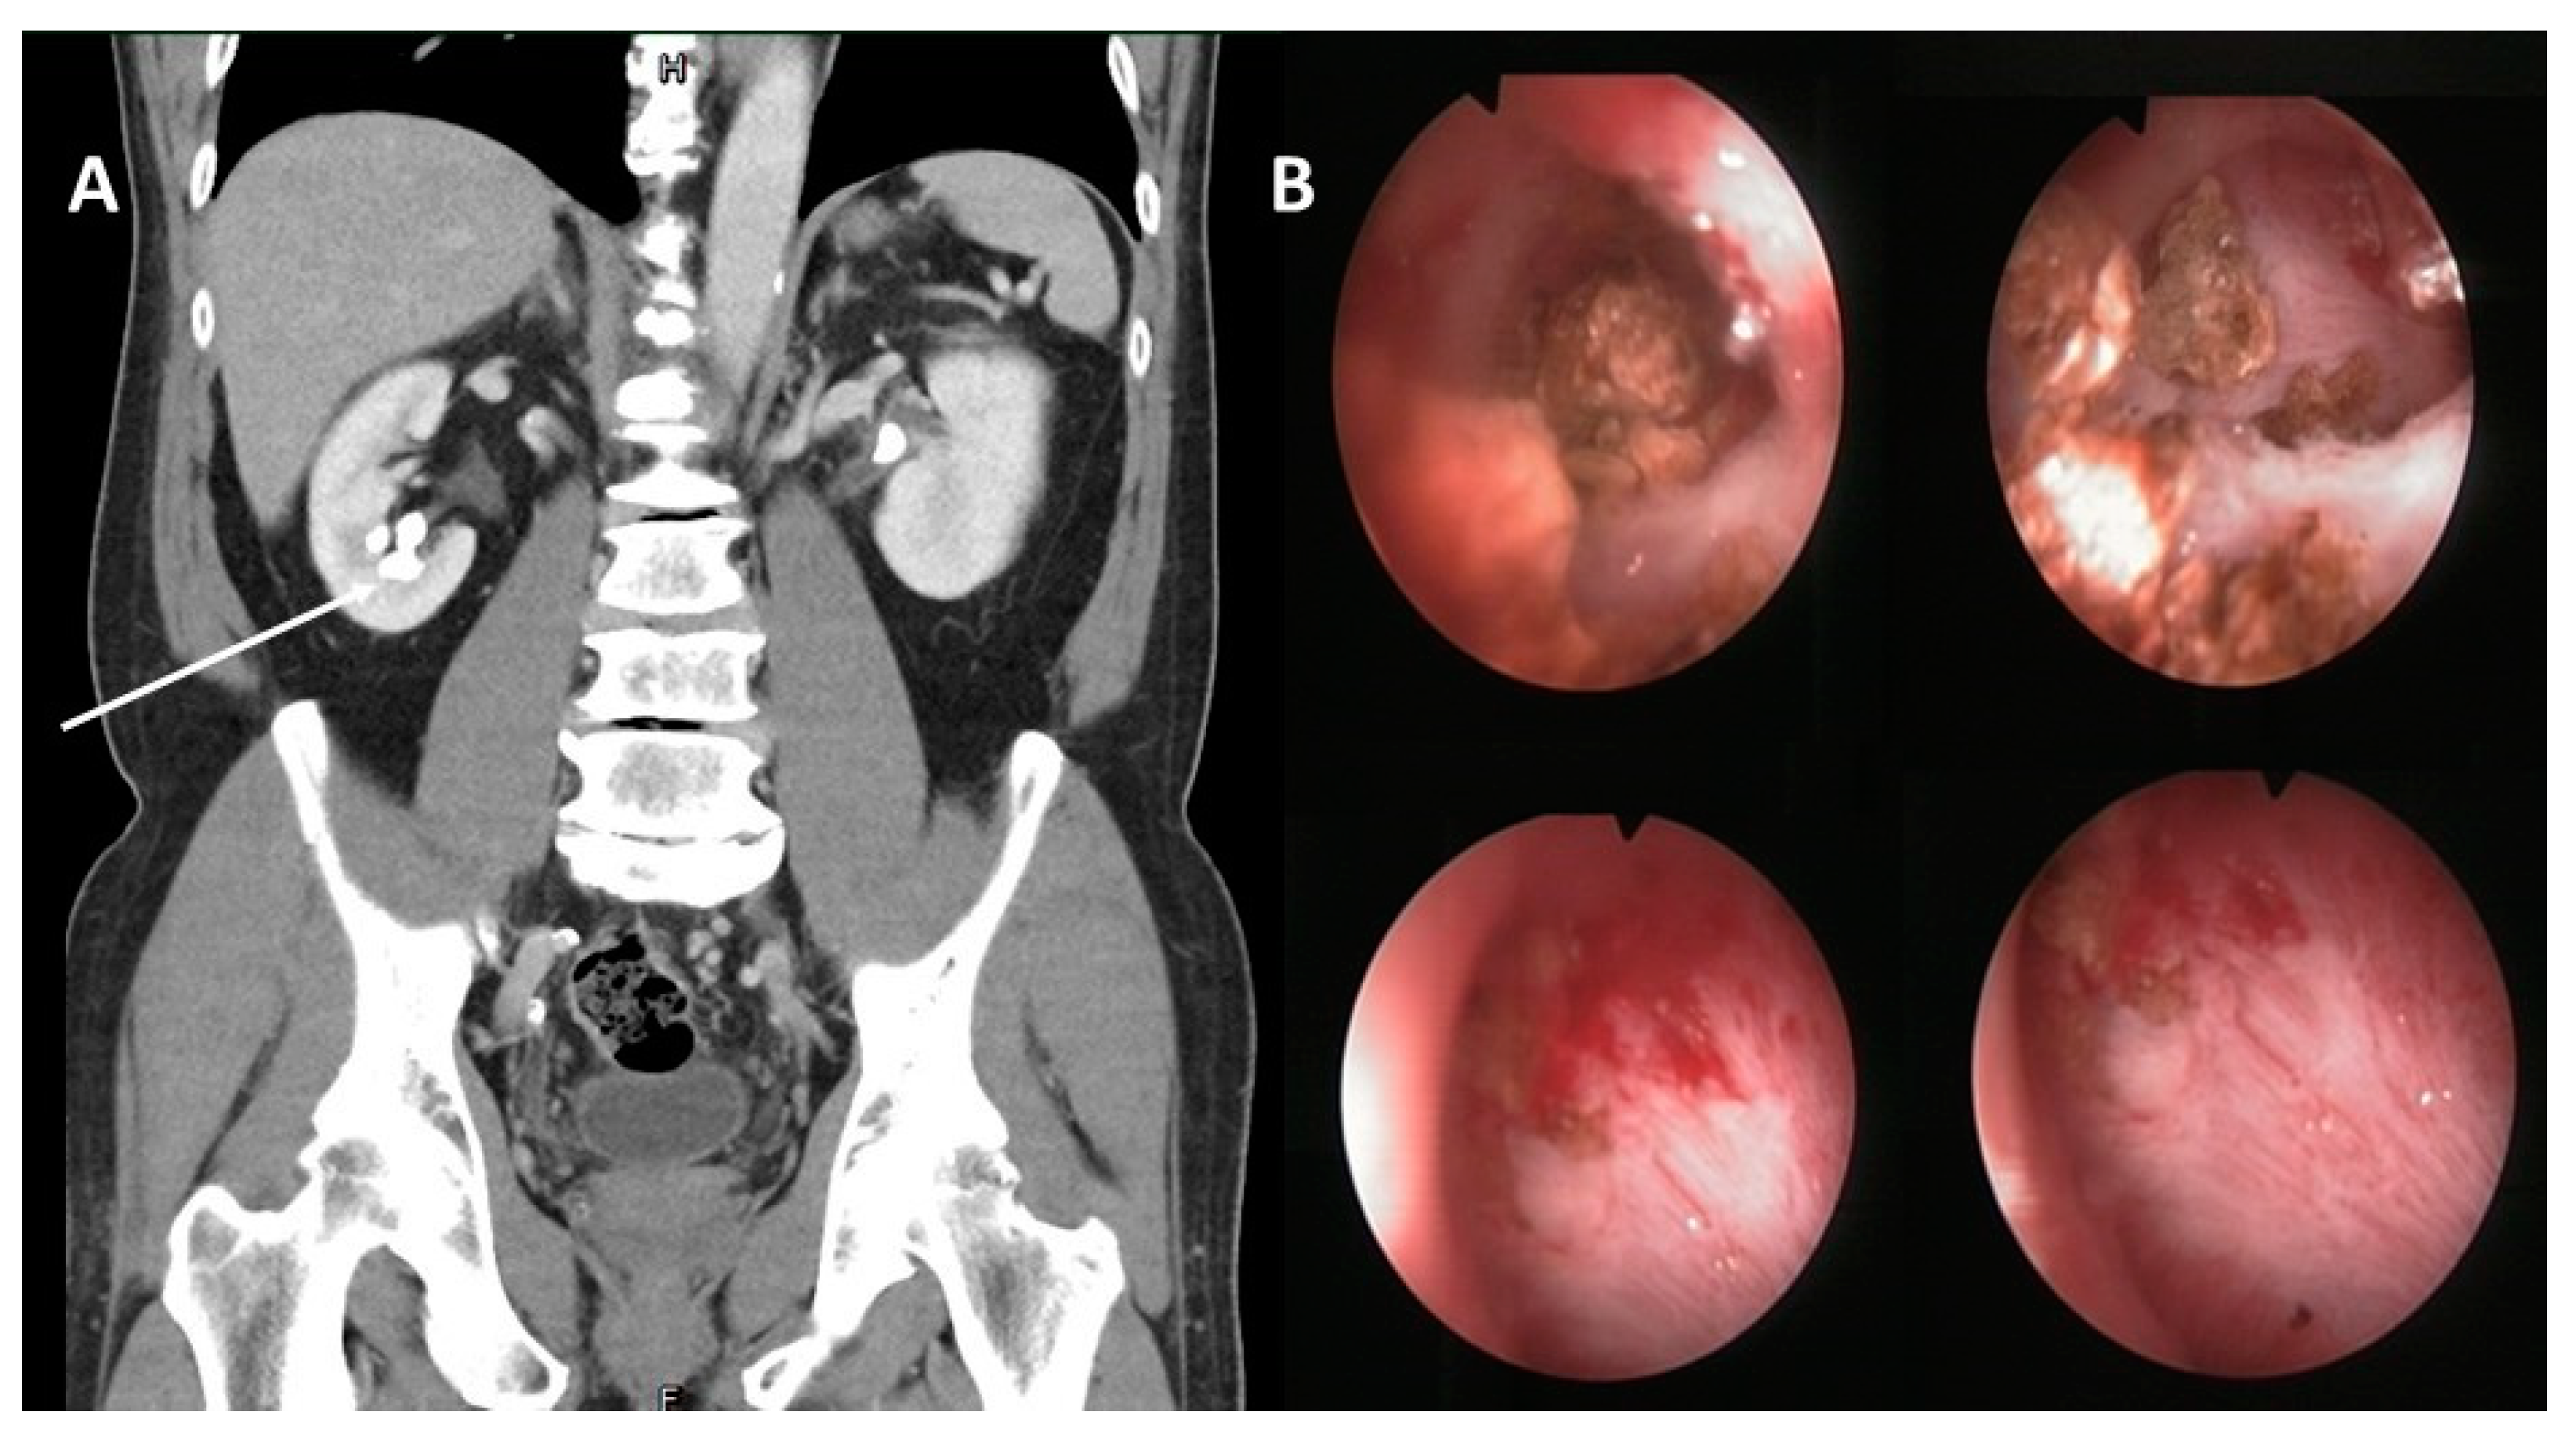

2. Case Presentation